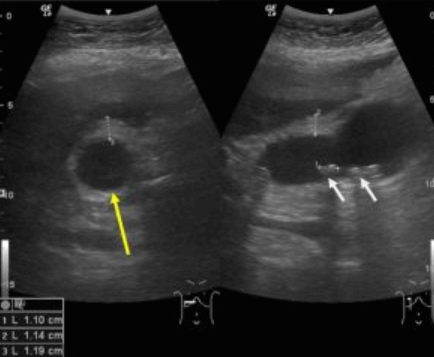

급성담낭염 US finding

- 담낭관내 결석

- 담낭벽이 두꺼워진다 ( GB wall thickness 3mm 이상)

- GB내강의 압력증가 및 확장 (width 5cm 이상)

- color doppler 시 GB wall 혈류증가 GB lumen bile sludge (내부에코증가)

- 급성담낭염은 담낭주위 액체저류 (pericholecystic fluid)

- 심한 RUQ pain (Murphy sign) : 젊은 환자에서는 대부분 Murphy sign이 있지만, 노인에서는 Murphy sign이 없더라도 급성 담낭염이 있는 경우가 많으므로 더 주의 깊게 관찰해야 한다.